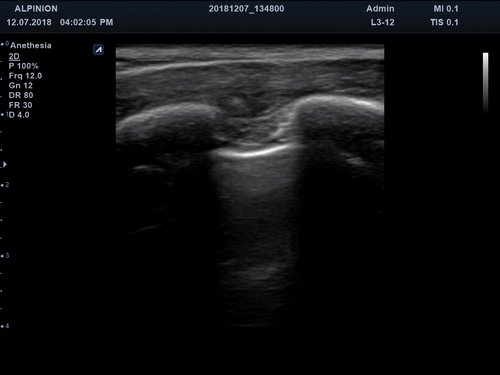

Eigenschaft minisono C1-6 minisono L3-12

Typ konvex linear

Frequenz 1 - 6 MHz 3 - 12 MHz

Maße (Länge/ Breite/ Höhe) 25,5/ 62,5/ 157mm 25,2/ 62,5/ 150mm

Gewicht 5,8 oz/ 175g 5,6 oz/ 165 g

Scan-Tiefe 30 cm 10 cm

Sichtfeld 78 ° 38,4 mm

Display Microsoft Surface Microsoft Surface

Batterielaufzeit 300 min 300 min

Anwendungsbereiche Abdomen MSK, Nerven, Karotis, periphere Gefäße, Schilddrüse, Mamma

Bildgebungs-Modi B-Modus, CF, M, PW, PD B-Modus, CF, M, PW, PD

Das minisono-Ultraschallsystem ist mit folgenden Technologien ausgestattet:

• B-Modus: Darstellung zweidimensionale Bilder anatomischer Strukturen

• PW-Doppler (Pulsed-Wave): Verfahren, das ein Geschwindigkeitsspektrum von beweglichem Gewebe und Flüssigkeiten an einer bestimmten Position liefert

• Farbdoppler: farbige Darstellung der Richtung des Blutflusses